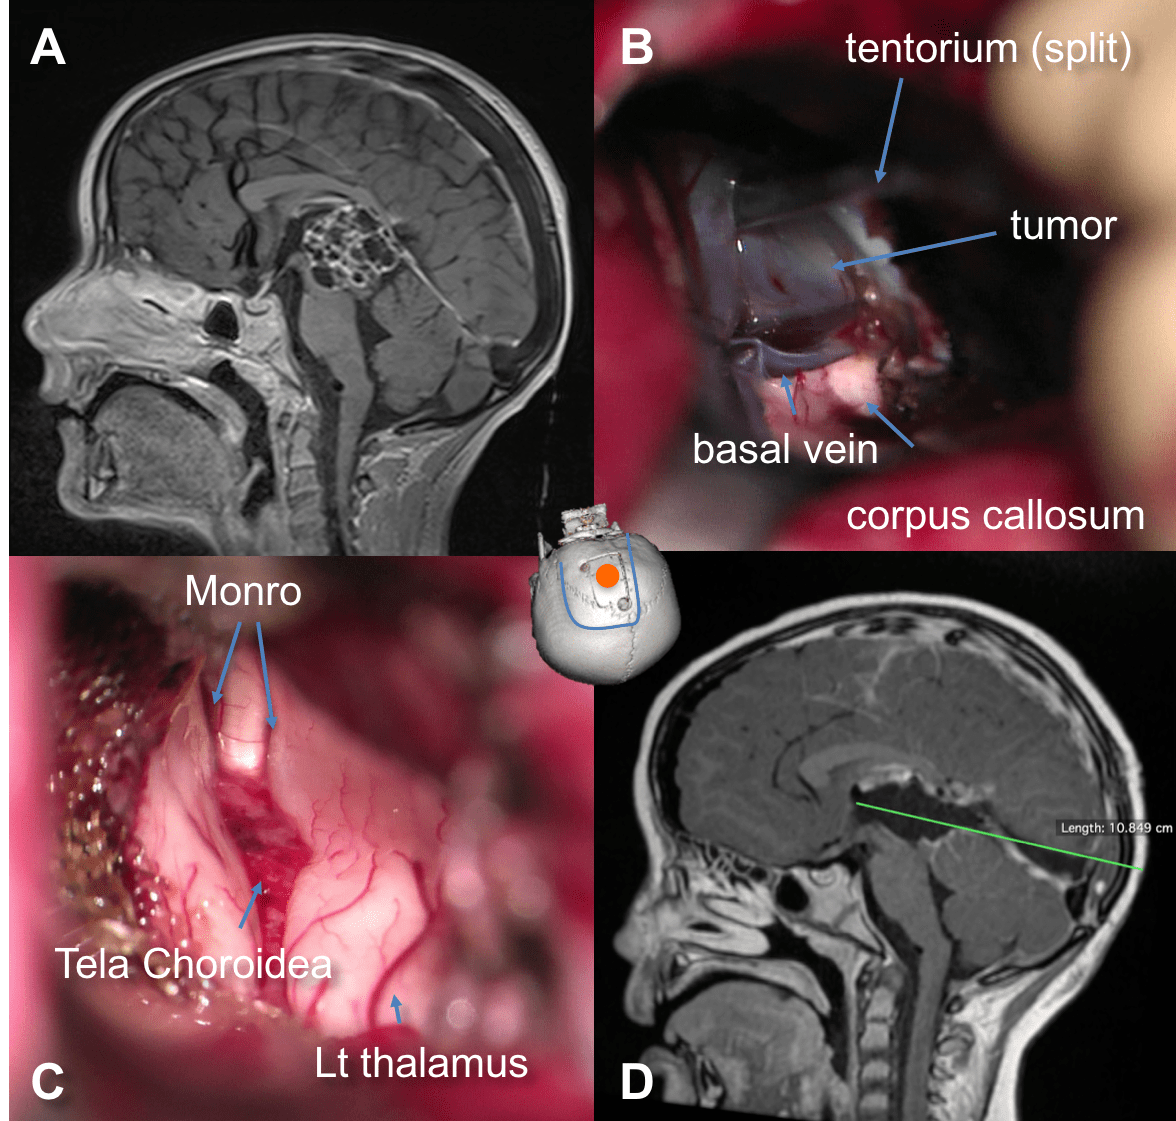

A: exposition of the tectal tumor after splitting of the tentorium; B: section of the precentral vein allowing access to the tectal plate and third ventricle - la tumeur est disséquée des veines adjacentes, en particulier les veines cérébrales internes auxquelles elle peut adhérer (tératomes résiduels après chimiothérapie)

secreting tumor diagnosed in April; under chemotherapy, negativation of tumor markers while the tumor shows considerable progression

il est plus adapté pour les tumeurs développées vers l’arrière (pointe du vermis) et les lésions de petite taille s’étendant dans le V3 au contact des veines cérébrales internes. il peut également être nécessaire lorsque l’espace entre la tente du cervelet et le corps calleux est très étroit, en particulier pour accéder à la cavité du 3ème ventricule ; cette voie donne alors un bon contrôle de la face inférieure de la toile choroïdienne et des veines cérébrales internes.